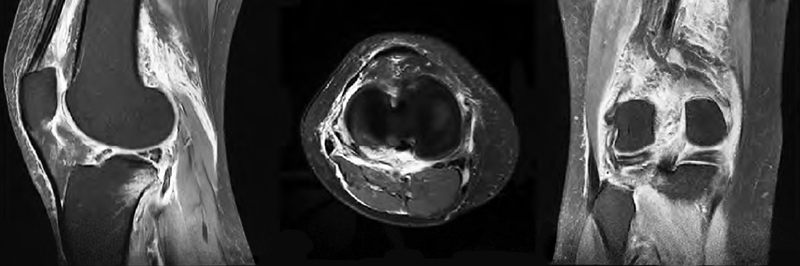

影像学检查:膝关节正侧位 X线片未见明显骨折。右膝关节MRI显示:右膝关节退行性变;胫骨平台后方骨挫伤,考虑股骨下端关节面下少许骨挫伤,考虑前交叉韧带及内侧副韧带损伤;内外侧半月板前后角Ⅱ~Ⅲ度表现,关节囊积液,关节周围软组织挫伤、肿胀(图2)。

图2 术前矢状面、横断面、冠状面 MRI示外侧半月板三度损伤